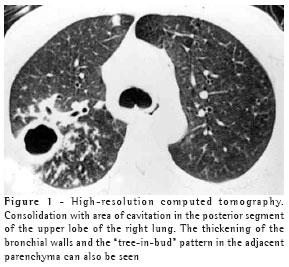

The most frequent finding in the imaging, present in the seven patients, was ill-defined consolidation (Figures 1, 2, 3 and 4). Five of patients presented air bronchogram, principally at the periphery of the lesion. In three cases, the consolidation was organized in the form of a mass. In six of the seven patients, irregular areas of cavitation were observed within the consolidations. Multiple cavitations were seen in five patients, and a singular cavitation was observed in one patient. In the patient presenting no cavitation, there were hypodense areas suggestive of necrosis (Figure 5). Only one of the patients presented air-fluid levels within the cavities.

Cavitated lesions predominated in the upper lobes, four in the right lobe and one in the left lobe. In one patient, the middle lobe was also affected. In two cases, such lesions occurred in the lower lobes, one in the right lobe and one in the left lobe. In four cases, the lesions affected only the lobes mentioned above and were therefore unilateral. In the remaining three cases, the contralateral lung was also affected, albeit to a lesser degree. In one case, there was also relatively thin-walled, multiloculated cavitation, without an air-fluid level, in the middle lobe.

Ground glass opacities, primarily surrounding the cavitated lesions, were reported in six patients, although this was not the predominant finding in any of the cases.

In our study, the principal pattern of pulmonary involvement was air bronchogram and cavitation, which was present in six patients. There were multiple cavitations in five cases and a singular cavitation in one. The consolidations were large and had irregular contours. The air bronchograms were located in the peripheral portions of the lesions. The pulmonary lobe most frequently involved was the upper right lobe, which was affected in four patients. Most of the case review studies confirm these findings.(2,5) Some studies have reported that, although cavitation might not be present at the time of diagnosis, it develops over the course of the disease.(4) In the sample evaluated in the present study, air-fluid levels within the cavitations were seen in only one patient.

Other findings were ground glass opacities, peribronchial nodules, small nodules of predominantly centrilobular distribution, and the "tree-in-bud" pattern. These alterations were predominantly seen surrounding the cavitated consolidations. In one case, they were also present in both of the lower lobes. It is believed that this finding indicates bronchogenic dissemination of the infection.